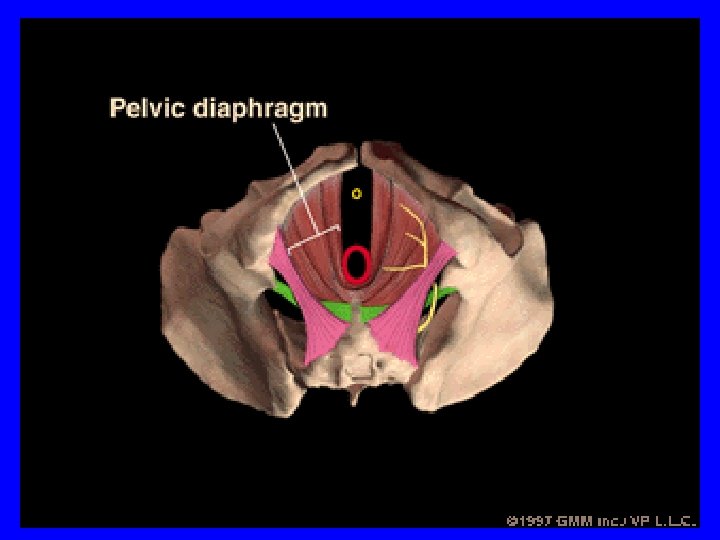

• 1. Western conservative treatment • Conservative treatment mainly includes pelvic floor muscle exercises (PFME), electrical stimulation (ES), various vaginal and urethral devices and medication. • PFME and transvaginal or trans-anal ES (TES) are the two most commonly used forms of conservative treatment for SUI. • 保守治疗主要包括盆底肌锻炼、电刺激、 各种阴道和尿道装置及药物治疗。其中 盆底肌锻炼和经阴道或肛门电刺激(被 动的盆底肌锻炼)是最常用的二种治疗 方法。

• 1. Western conservative treatment • PFME can build up the structural support of the pelvis, improve neuromuscular function, prevent the proximal urethra and bladder base from descending during a rise in abdominal pressure and increase urethral pressure. • 盆底肌锻炼具有增强盆底肌肉支持力量, 改善神经肌肉功能,阻止腹内压增高时 近端尿道和膀胱底部下降及增加尿道压 的作用。

• 3. Electroacupuncture pudendal nerve stimulation • By combining the advantages of PFME and TES and incorporating the technique of deep insertion of long needles, we developed electracupuncture pudendal nerve stimulation ( “Four sacral points” electracupuncture therapy), which is a combination of traditional Chinese and Western medicine. • 3. 电针阴部神经刺激疗法 • 综合PFME 和 TES二种疗法优点,融入针灸长 针深刺技术,我们发展成了(中西医结合的)电 针阴部神经刺激疗法(电针“骶四穴”疗法)。

• 3. Electrical pudendal nerve stimulation • In this therapy, four sacral specific points are acupunctured by a special needling method (the needle tip in a specific direction) and electrified • 3. 电针阴部神经刺激疗法 • 该疗法对骶部四个特定穴位采用特殊针 刺方法(针尖向特定方向)并加以电刺 激

• 3. Electrical pudendal nerve stimulation • to improve the ability in controlling urination by exciting the pudendal nerve and inducing the rhythmic contraction of the pelvic floor muscles (including the urethral sphincter ) to strength the muscles, restore the normal positions of bladder neck and proximal urethra and increase urethral closure pressure. • 能直接兴奋阴部神经诱发盆底肌(包括 尿道括约肌)节律性收缩,从而增强盆 底肌肉力量,恢复膀胱颈部和近端尿道 的正常位置,提高尿道关闭压来改善控 尿能力。